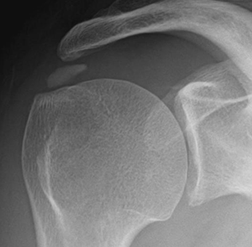

En la Rx se identifica la calcificación medial o superior a la tuberosidad mayor.

Fig 139. Tendinitis crónica del supraespinoso.

Rx AP. Calcificación alargada sobre la topografía del tendón del supraespinoso, por tendinitis crónica.